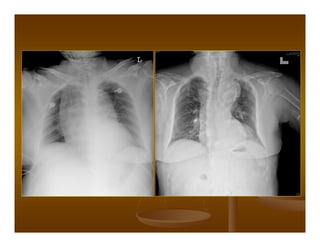

Following pericardial tap and air

injection air-fluid level (large

arrow),true cardiac border

(small arrows),note the normal

thickness of the pericardium.

Sau khi chọc hút dịch màng tim